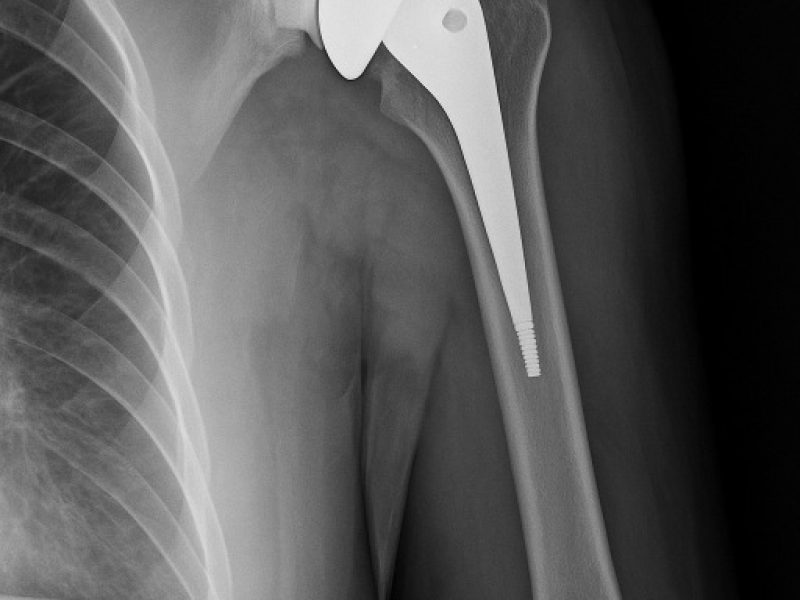

Il dolore alla spalla e la perdita di mobilità possono compromettere attività quotidiane semplici come vestirsi, sollevare il braccio o dormire senza fastidio. Quando l’articolazione è gravemente danneggiata, la protesi inversa di spalla rappresenta una soluzione efficace per recuperare funzione e ridurre il dolore.

Questa tecnica è particolarmente indicata nei pazienti con lesioni irreparabili della cuffia dei rotatori o con artrosi avanzata della spalla.

Tecnica Chirurgica Avanzata

La protesi inversa modifica la biomeccanica naturale dell’articolazione, permettendo al muscolo deltoide di sostituire la funzione dei tendini danneggiati.

I principali vantaggi sono:

Riduzione significativa del dolore

Recupero della mobilità del braccio

Maggiore stabilità articolare

Miglioramento della qualità della vita

Un Percorso Personalizzato

Ogni intervento viene pianificato attentamente attraverso esami diagnostici e valutazione clinica completa, per scegliere la soluzione più adatta al paziente.

Recupero Funzionale

Grazie a protocolli riabilitativi mirati:

La mobilizzazione inizia precocemente

Il recupero della funzionalità avviene gradualmente

Il paziente viene seguito costantemente durante tutto il percorso di recupero.